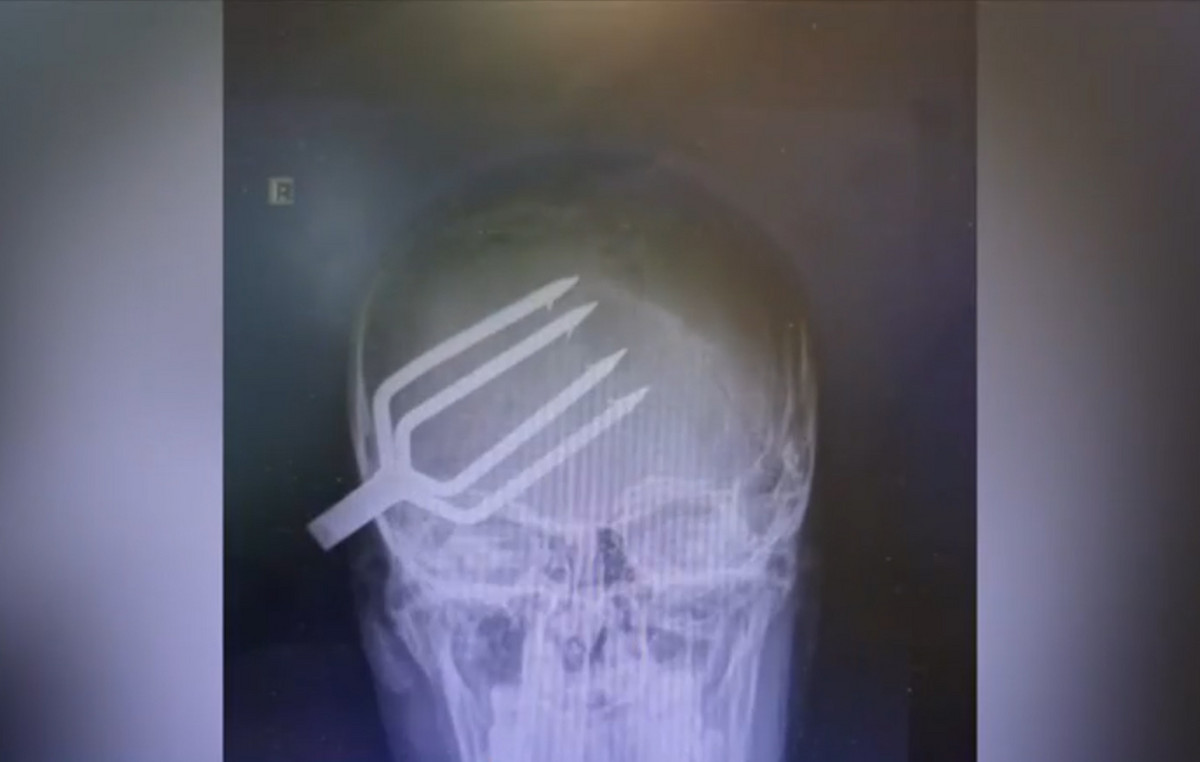

Βγήκε από το νοσοκομείο ο 14χρονος που του είχε καρφωθεί καμάκι από ψαροντούφεκο στο κρανίο

Εξιτήριο πήρε ο 14χρονος που είχε τραυματιστεί σοβαρά στο κεφάλι από καμάκι ψαροντούφεκου στη Χαλκιδική. Ομάδα παιδιών έπαιζαν όταν καρφώθηκε το καμάκι στο κρανίο του 14χρονου. Σύμφωνα με τον Alpha, ο 14χρονος ήταν τυχερός γιατί για χιλιοστά το τραύμα δεν απέβη μοιραίο. Ειδική ομάδα γιατρών αφαίρεσε το καμάκι από το κρανίο του και το παιδί πήρε εξιτήριο  σήμερα από το νοσοκομείο.